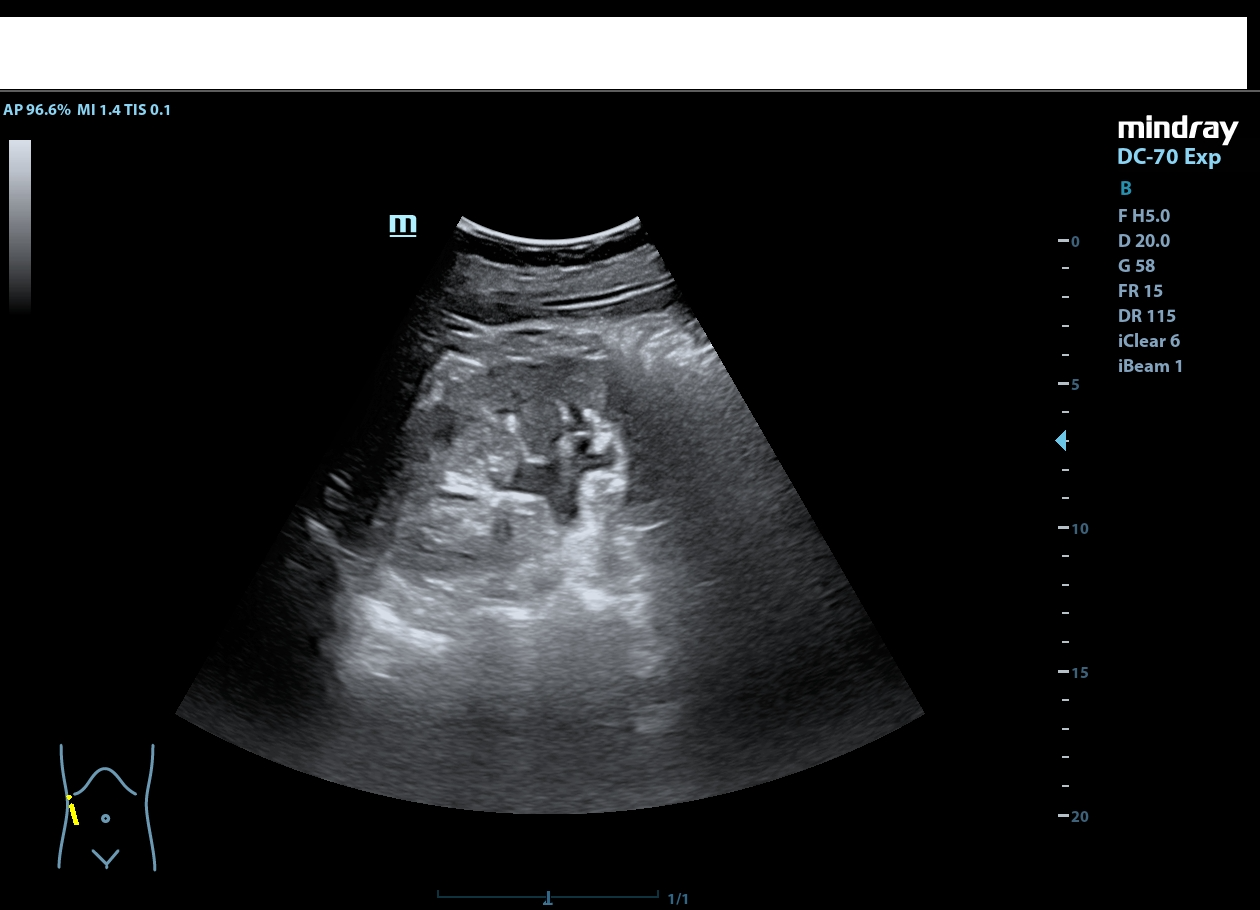

Descripción de los hallazgos ecográficos y las imágenes más relevantes para la resolución del caso

Riñón derecho de ecoestructura conservada, con dilatación pielocalicial grado I. Riñón izquierdo con adelgazamiento cortical y ureterohidronefrosis grado IV, sin poder localizarse el origen de la obstrucción, ausencia de jet ureteral izquierdo. Hallazgos sugestivos de síndrome de la unión pieloureteral.